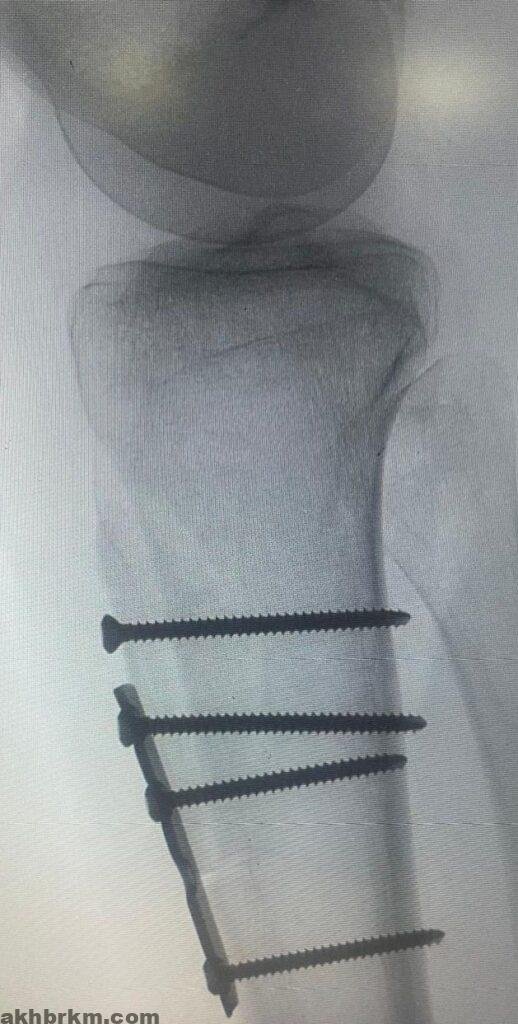

وتفصيلا قال الدكتور فهد الحليبي، استشاري جراحة العظام والإصابات الرياضية المعقدة ، ان المريضة حضرت لمجمع الدمام الطبي وهي تعاني من خلع متكرر في عظمة الرضفة بالركبة لعدة سنوات بالاضافة الى اختلال ديناميكية اوتار الركبة . حيث تقرر اجراء عملية قص جذر وتر عظمة الرضفة وتغيير مسارها وتثبيتها جراحياً، إلى جانب إجراء تثبيت جانبي لنفس العظمة باستخدام وتر العضلة الخلفية بتقنية المنظار الجراحي.وتتمتع المريضة بصحة جيدة بعد توفيق الله وتتابع التأهيل بمركز العلاج الطبيعي بالمجمع للوصول الى افضل النتائج .

وأكد ” الحليبي ” أن هذه الجراحة تُعد من العمليات النادرة في مجال جراحة العظام، حيث تتطلب خبرة ومهارة عاليتين، موضحاً أن مثل هذه الحالات كانت تُحول سابقاً إلى مراكز طبية خارج المنطقة ، مسلطا الضوء على التطور الكبير الذي حققه مجمع الدمام الطبي في مجال جراحة العظام. و دليلاً على التقدم الملحوظ الذي احرزه في علاج الحالات النادرة والمعقدة، وذلك بالاعتماد على أحدث التقنيات الطبية وتوفير فرق طبية مؤهلة للتعامل مع أدق العمليات الجراحية، مما يُسهم في الارتقاء بمستوى الخدمات الصحية المقدمة للاهالي في المنطقة الشرقية .